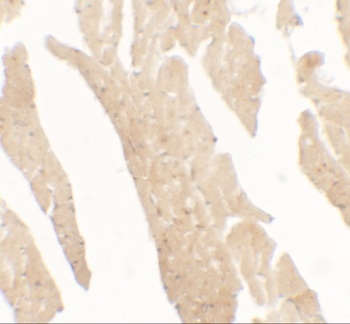

Immunohistochemistry of paraffin-embedded human colon cancer tissue using IL36RN antibody

Immunohistochemistry of paraffin-embedded human skin tissue using IL36RN antibody